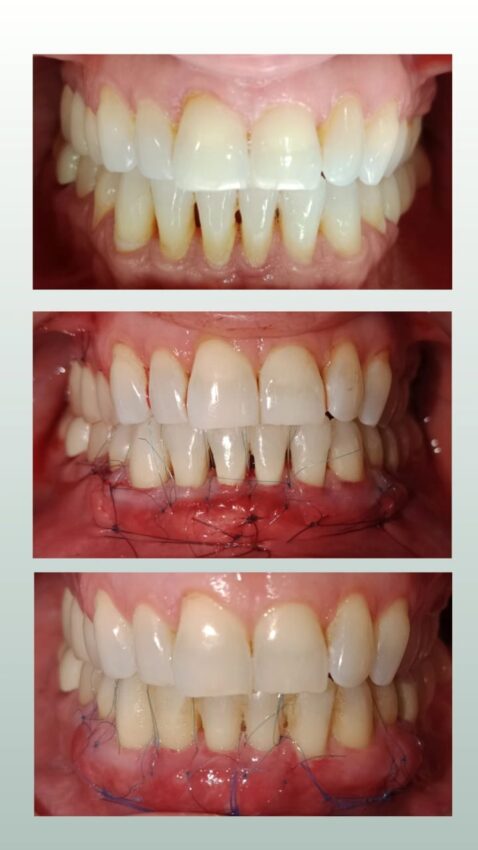

Periodoncia